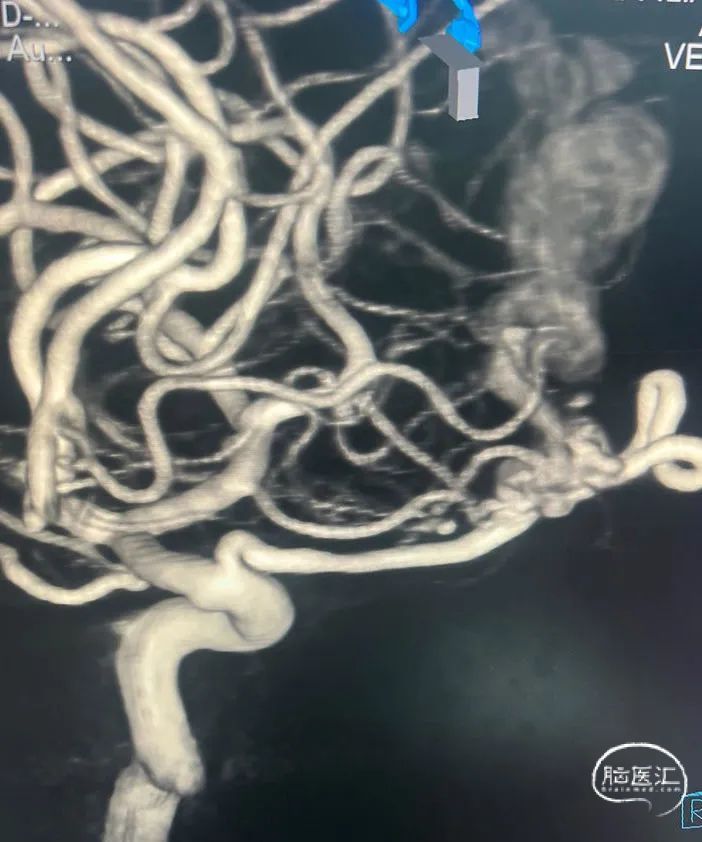

左边栓塞后,右侧颈内动脉3d旋转,仍然发现有瘘口残留,乘胜追击,一不做,二不休,既然病人决定要介入治疗,我们应该"连根铲除",避免复发。

左侧眼动脉栓塞术后。

右侧,想想左侧拔管的情况比较后怕,故换用Apollo,只能用HyperForm球囊,远端阻断提供支撑力,让Apollo进到瘘口。

微导管到位后的微导管造影情况,位置满意,斩草除根。

右侧眼动脉路径栓塞术后。

最后的onyx18胶-3d铸形,达到了治愈性栓塞的目的,病人也免得开颅之折腾。